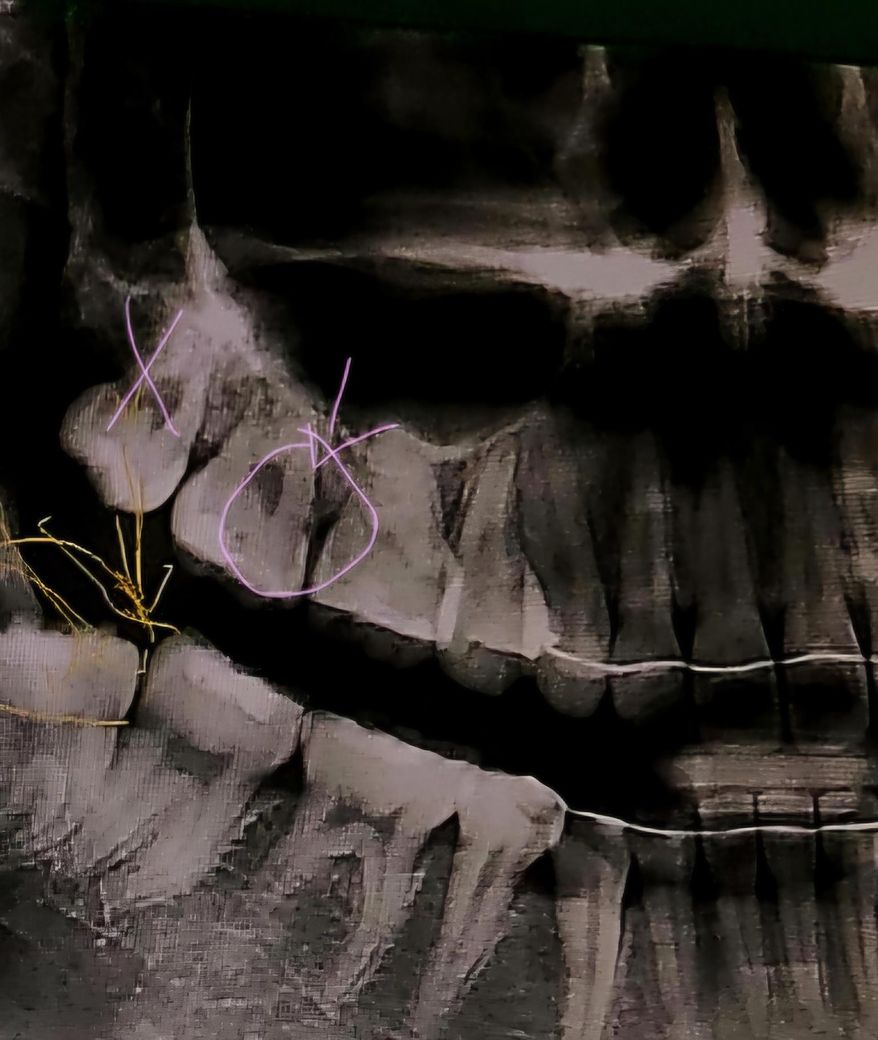

• 2번 째 사진